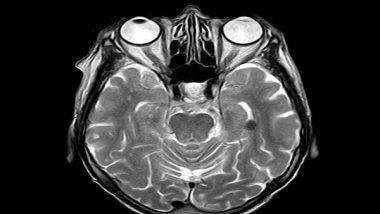

Washington [US], December 30 (ANI): A team of engineers and neuroscientists has demonstrated for the first time that human brain organoids implanted in mice have established functional connectivity to the animals' cortex and responded to external sensory stimuli. The implanted organoids reacted to visual stimuli in the same way as surrounding tissues, an observation that researchers were able to make in real time over several months thanks to an innovative experimental setup that combines transparent graphene microelectrode arrays and two-photon imaging.

Human cortical organoids are derived from human induced pluripotent stem cells, which are usually derived themselves from skin cells. These brain organoids have recently emerged as promising models to study the development of the human brain, as well as a range of neurological conditions.

But until now, no research team had been able to demonstrate that human brain organoids implanted in the mouse cortex were able to share the same functional properties and react to stimuli in the same way. This is because the technologies used to record brain function are limited, and are generally unable to record activity that lasts just a few milliseconds.

By placing an array of these electrodes on top of the transplanted organoids, researchers were able to record neural activity electrically from both the implanted organoid and the surrounding host cortex in real time. Using two-photon imaging, they also observed that mouse blood vessels grew into the organoid providing necessary nutrients and oxygen to the implant.

Researchers applied a visual stimulus-an optical white light LED-to the mice with implanted organoids, while the mice were under two-photon microscopy. They observed electrical activity in the electrode channels above the organoids showing that the organoids were reacting to the stimulus in the same way as surrounding tissue. The electrical activity propagated from the area closest to the visual cortex in the implanted organoids area through functional connections. In addition, their low noise transparent graphene electrode technology enabled electrical recording of spiking activity from the organoid and the surrounding mouse cortex. Graphene recordings showed increases in the power of gamma oscillations and phase locking of spikes from organoids to slow oscillations from mouse visual cortex. These findings suggest that the organoids had established synaptic connections with surrounding cortex tissue three weeks after implantation, and received functional input from the mouse brain. Researchers continued these chronic multimodal experiments for eleven weeks and showed functional and morphological integration of implanted human brain organoids with the host mice cortex.